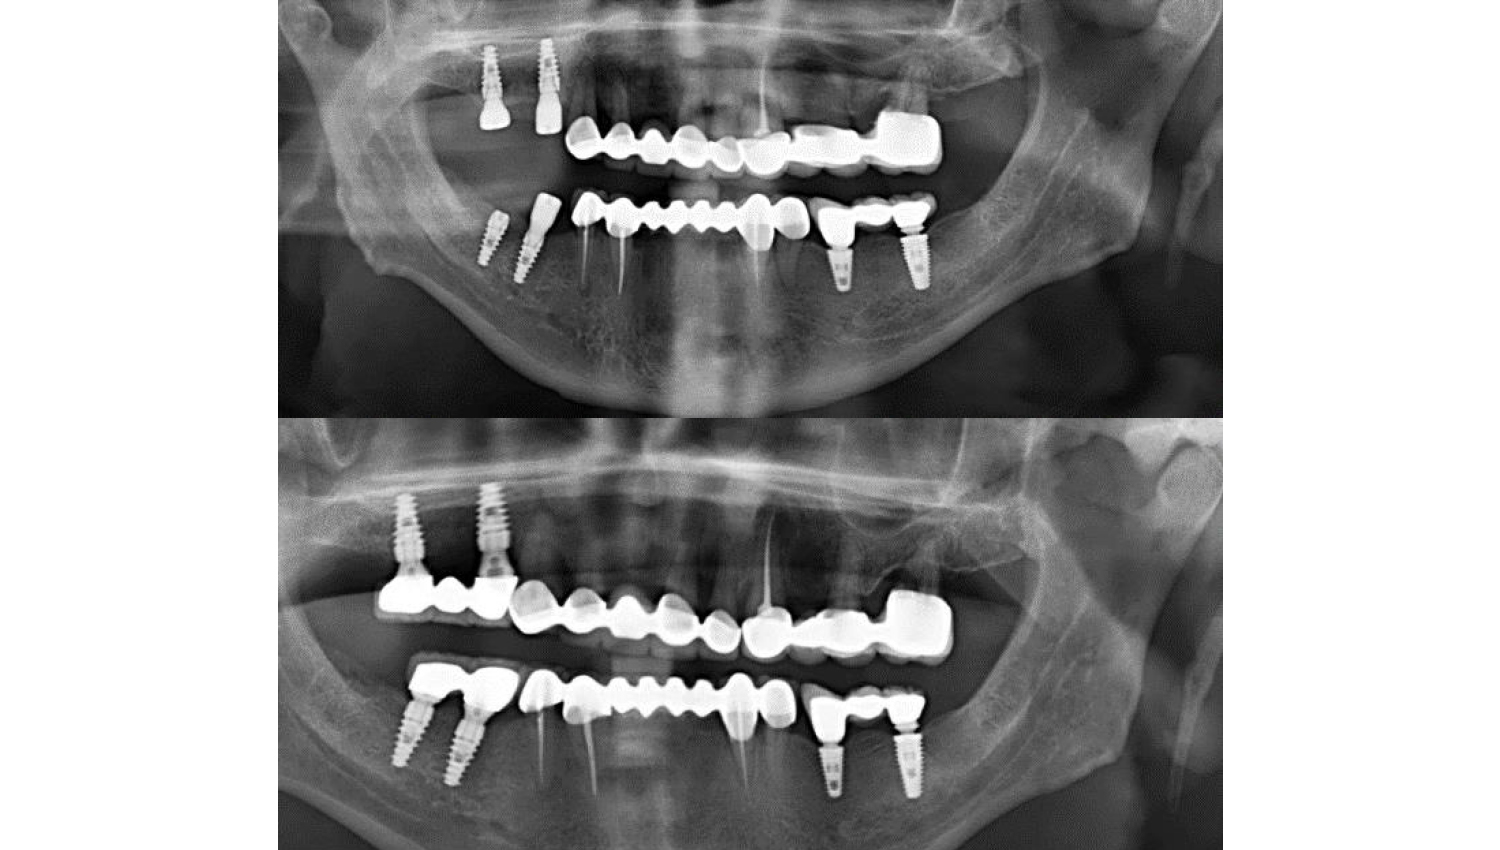

1.Initial radiological view.

3After Osstel measurements, implantation was performed with Powerbone Dental Implant. Radiological imaging after implantation is shown below.